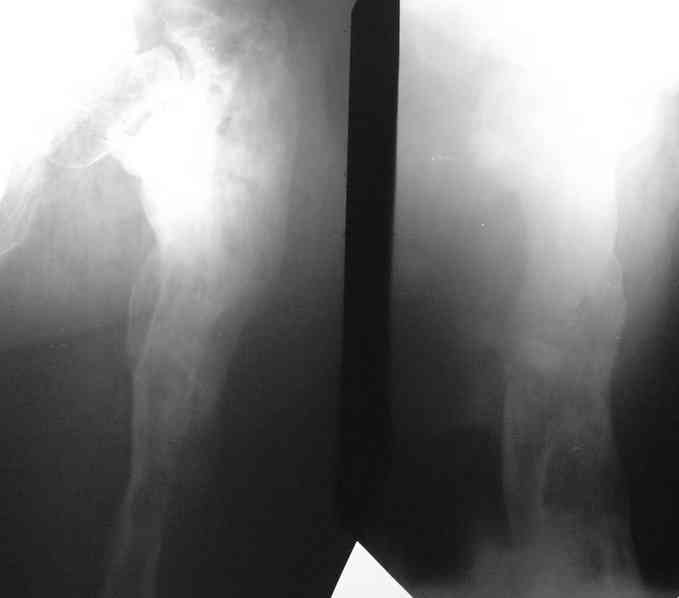

Больной 53 лет, страдает остеомиелитом с 1975г.,после закрытого перелома с/3 бедра и интрамедулярного остеосинтеза. Выполнено более 30 операций без особого эффекта. Какой комплекс операций может помочь больному? Больной, 1954 г.р.Клинический диагноз: хронический травматический тотальный остеомиелит левой бедренной кости, секвестрально - свищевая форма, часторецидивирующее течение. Ложный сустав шейки левой бедренной кости. Укорочение левого бедра 10 см. Контрактура коленного сустава. Жалобы: боли в области левого бедра, коленного сустава, нарушение функции левой ноги, наличие свища с гнойным отделяемым в левой подколенной области, свища в области в\з бедра. Анамнез: в 1975 г. получил закрытый перелом с\з левой бедренной кости. Оперирован в районной больнице - выполнена открытая репозиция, интрамедуллярный остеосинтез. Осложнение - нагноение раны с исходом в остеомиелит бедренной кости. В последующий годы - трижды патологический перелом бедра. Оперирован за эти годы около 30 раз по поводу обострения остеомиелита. За последние 5 лет обострения ежегодно по 2- 3 раза в год. Динамика отрицательная. Рентгенологически - тотальное поражение бедренной кости. Объективно: передвигается при помощи костылей с дозированной нагрузкой на левую ногу. При нагрузке на левую ногу - стопа в положении эквинуса, опора на передний отдел стопы. Выражена атрофия мышц левого бедра, голени. На всем протяжении бедра - множественные рубцы после оперативных вмешательств. В в\з бедра по наружной поверхности - грубый втянутый рубец с вялогранулирующей раной на дне его. Отделяемого нет. В области подколенной ямки - свищ с гнойным отделяемым серо - зелоноватого цвета без запаха. Укорочение бедра 10 см. Движения в тазобедренном суставе активно 180 - 160 град., пассивно 180 - 90 град. В коленном уставе 178 - 110 град. Чувствительных расстройств конечности нет.Лабораторные данные: Общ. ан. крови: 20.04.07. Нв-135 г\л, Er 4.22 млн., Le-9.7 тыс, Эоз. 4%, Пал.-5 %, Сегм.-60 %, Лимф. - 25 %, Моноц.-6 %, СОЭ 51мм\час.Биохимический ан. крови от 20.04.07г. Белок -77 г/л, сахар крови 5.38 ммоль/л., билирубин 10.2 мкмоль/л. Тимоловая проба 2.5 ед.пом. Ан.мочи от 20.04.07. : отн. плотность1026, белок - отр, сахар -отр, ЭКГ от 22.02.07 : отклонение ЭОС влево.. Неполная блокада правой ножки пучка Гиса. Флюорография от 28.12.2006 года № 038 - без патологии. R - графия : грубая деформация и склерозирование бедренной кости от проксимального до дистального метафиза , множество очагов просветления в области дистального метаэпифиза, н\з бедра. МРТ коленного сустава, н\з бедра от 21.04.2007г. - картина хронического остемиелита левой бедренной кости. Имеется полость деструкции в дистальном метадиафизе протяженностью до 12 см. Полость имеет неоднородное содержимое за счет гноя, грануляций, секвестров, сообщается со свищевым ходом, идущим в подколенную ямку.